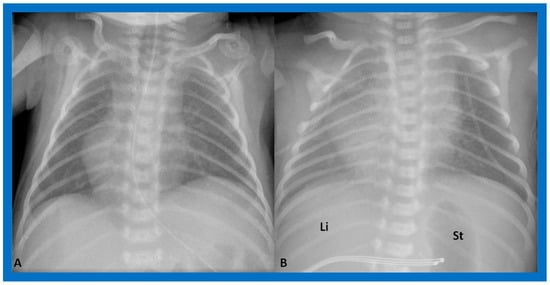

The heart is normally positioned in the left chest (Figure 1) and is designated levocardia.

Figure 1. Chest roentgenogram of a baby demonstrating the heart (H) in the left chest (L), i.e., levocardia. This is the usual position of the heart in most patients. The roentgenogram further demonstrates the liver (Li) on the right side of the abdomen and the gaseous opacity of the stomach (St) on the left side, again normal. This is described as situs solitus of the viscera. L indicates left. Reproduced from reference [4].

Figure 4. Chest X-rays of two neonates with their hearts in the middle of the chest, mesocardia. (A) The liver is visualized transversely in the abdomen; no gas bubble of the stomach (St) is seen. Therefore, visceroatrial situs cannot be determined with these findings. (B) The gaseous opacity of the St is visualized on the left side of the abdomen, and the liver (Li) is seen on the right, suggesting situs solitus. Reproduced from reference [4].

Situs solitus is a phrase used to characterize the normal location of the visceral structures in which the liver is located on the right side of the abdomen while the stomach is on the left side (Figure 1, Figure 3, Figure 4B and Figure 5).